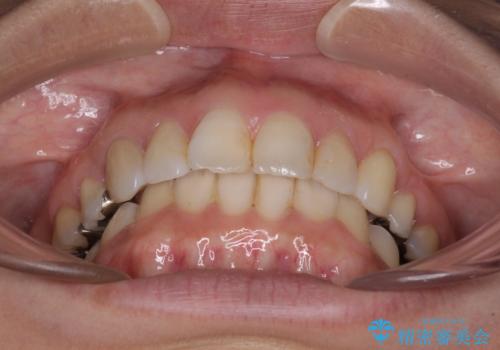

前歯の突出を軽減 インビザラインによる抜歯矯正

- 上の前歯の捻じれと突出感を気にして来院された患者様です。

目立たない装置を希望とのことで、上顎左右第一小臼歯を抜歯し、インビザラインにて矯正治療を行うこととしました。

インビザラインにて抜歯矯正を行うと、高頻度で奥歯が咬み合わなくなります。

抜歯スペースが閉じてからも咬みにくさ改善のためマウスピース矯正を継続するため、治療期間は長期化します。